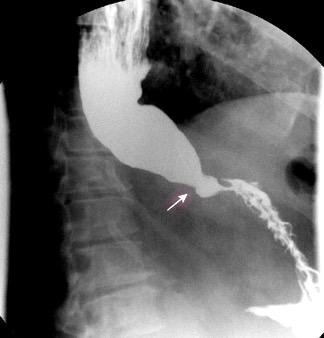

“Seudoquiste pancreático”

3 rasgos:

1. Conexión entre mediastino y lesión pancreática.

2. Derrame pleural

Matsusue E et al.Three cases of mediastinal pancreatic pseudocysts. Acta Radiol Open. 2016 .

3. Hallazgos de pancreatitis. Panda A et al. “Straddling Across Boundaries”. Thoracoabdominal Lesions: Spectrum and Pattern Approach.Curr Probl Diagn Radiol, 2015